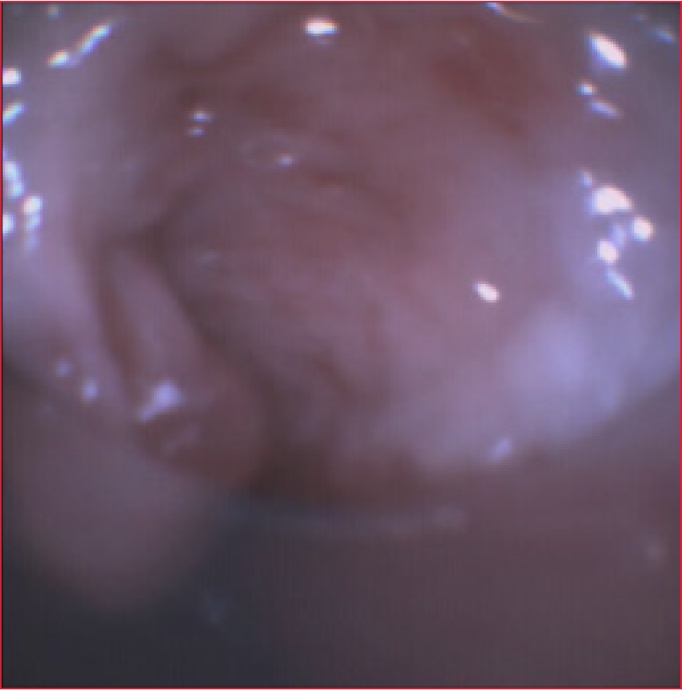

La broncoscopia flexible que se realizó por la cánula de traqueostomía mostró una membrana grisácea y anular que estaba adherida a la pared traqueal posterior a nivel del extremo distal de la cánula de traqueostomía (Figura 1). Además, se visualizaba un sector desprendido que se movía libremente en la vía aérea con el ciclo respiratorio para obstruir casi por completo la cánula de traqueostomía en forma de válvula (Figura 2). Ante la imposibilidad de aspirarlo, se decidió asegurar la vía aérea mediante la intubación endotraqueal. Al retirar la cánula, se extrajo parte de la seudomembrana.

Figura 1. Evaluación endoscópica realizada por

la cánula de traqueostomía. Se observa una seudomembrana grisácea adherida a la

pared posterior de la tráquea.

Figura 2. Sector móvil de la seudomembrana que

obstruye intermitentemente la luz de la cánula de traqueostomía.